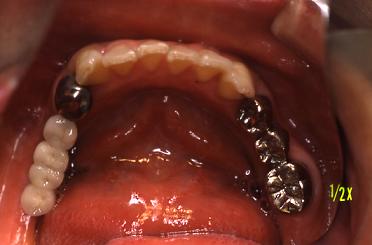

仮り歯を入れました

(術直後)